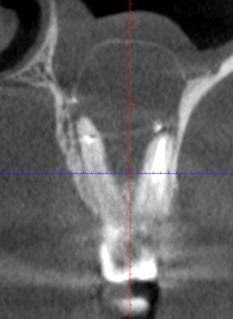

Вот другой пример кисты:

Это ещё киста вокруг зуба. И в данном случае только на томограмме можно увидеть купол.

Лечение зуба без хирургии бесперспективно. Зуб не спасти, если не убрать кисту. Киста растёт в пазуху вокруг зуба, деформируя её. В конце удаляли вместе с верхушками корней.

Здесь пациент хотел имплантацию. Как и всегда, врачи сначала снимают, потом планируют, а не сверлят по наитию: это гарантирует, что врач не воткнётся в нерв, сосуд или ещё куда-то, куда не надо. Без КТ в принципе не стоит делать никакого серьёзного вмешательства. В данной ситуации, если бы операцию делали в клинике классом ниже без КТ, имплантация была бы обречена на провал.